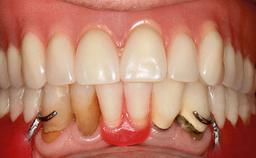

Improving an Existing Implant-supported Denture in an Alzheimer Patient with Bipolar Affective Disorder with Moderate Depression and Dementia

An 83-year-old man presented together with his caregiver at the dental department of the Medical University of Innsbruck, Austria with complaints of swelling in the right maxillary canine area and loss of retention of his 5-years-old mandibular denture. The patient had a significant medical history (20 years) of bipolar affective disorder with moderate depression (F 31.3) and dementia in Alzheimer’s disease (F 00.2). The patient had been in ambulant psychiatric therapy for his depressive illness for the past 20 years. He lived alone and had no children; his sister assisted with daily living. She reported that the patient exhibited compulsive hoarding behavior. In the previous two months, she had noted increasing disorientation and vertigo in the patient. She therefore accompanied him for a medical consultation at the Department of Psychiatry and Psychotherapy of the Medical University of Innsbruck. He was released home after a 6-week inpatient stay.